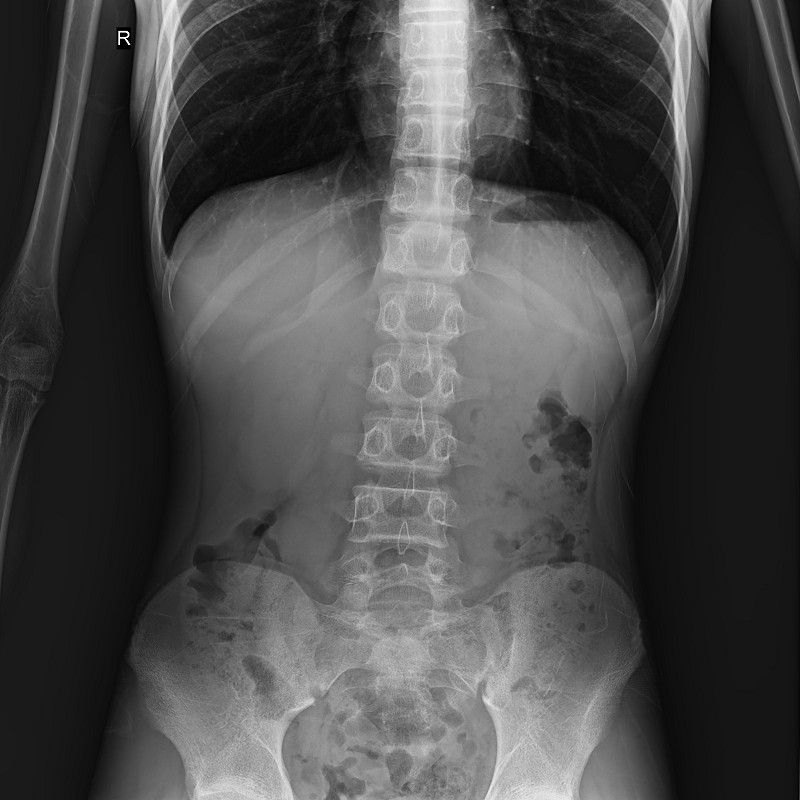

全自動(dòng)拼接

●呈現(xiàn)全下肢或全脊柱圖像

●在脊柱及下肢畸形矯正手術(shù)治療中,為術(shù)前方案制定和術(shù)后復(fù)查提供精準(zhǔn)測(cè)量

●有效解決傳統(tǒng)X光片不能一次成像問題,為患者提供更加優(yōu)質(zhì)的醫(yī)療服務(wù)

Clinical picture

臨床圖片